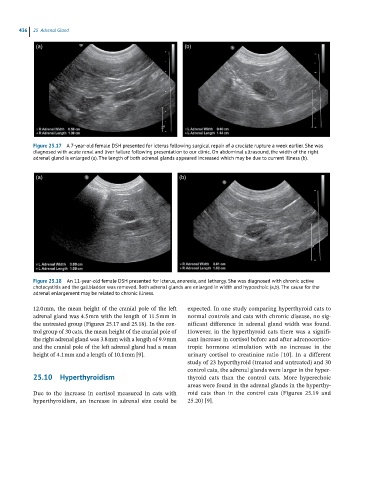

Figure 25.17 A 7-year-old female DSH presented for icterus following surgical repair of a cruciate rupture a week earlier. She was

diagnosed with acute renal and liver failure following presentation to our clinic. On abdominal ultrasound, the width of the right

adrenal gland is enlarged (a). The length of both adrenal glands appeared increased which may be due to current illness (b).

Figure 25.18 An 11-year-old female DSH presented for icterus, anorexia, and lethargy. She was diagnosed with chronic active

cholecystitis and the gallbladder was removed. Both adrenal glands are enlarged in width and hypoechoic (a,b). The cause for the

adrenal enlargement may be related to chronic illness.